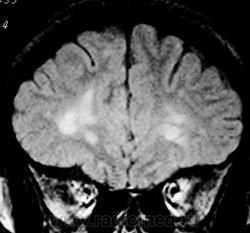

ГМ. Рассеянный склероз 3. +

Рассеянный склероз